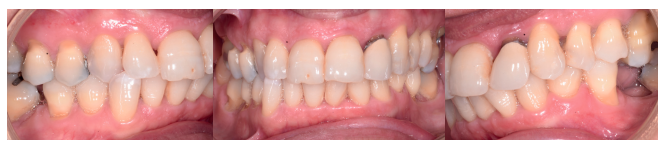

Tras 3 meses de la colocación del implante, se realizó la segunda fase, mediante una incisión horizontal palatinizada, para desplazar el tejido en una dirección vestibular (Figura 10). Se pudo apreciar el aspecto homogéneo del injerto de dentina, en contacto con el pilar de titanio (Figura 11), que fue rebasado con acrílico para la colocación de una corona provisional (Figuras 11 y 12). A la semana de la segunda fase, se valoró el aspecto del tejido gingival y la óptima ganancia de tejido a nivel horizontal (Figura 13).

palatinizada.

de titanio para rebasar y confección de corona de resina

provisional (B-D).

post-operatorio inmediato.